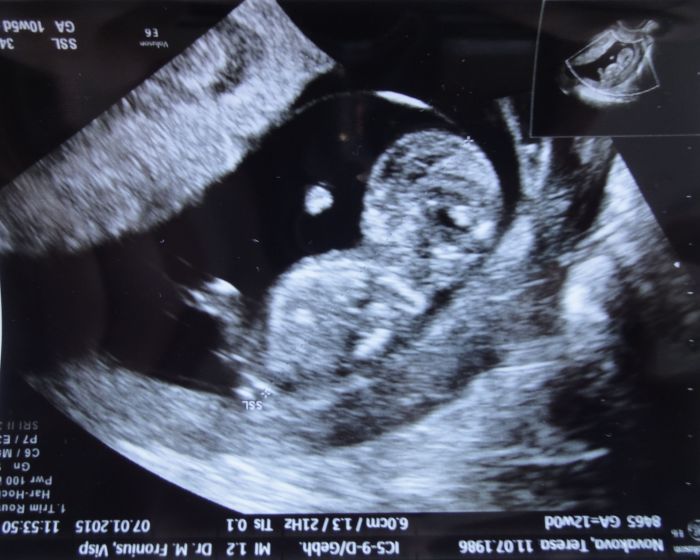

Holky, tak mám to taky za sebou. 1. návštěvu... hurá a opravdu tam je. Vážily mě, měřily tlak (kapku vysoký-141/89), braly krev (řešili jsme rh-faktory), moč (docela koukali, když jsem ji donesla z domu ve zkumavce (vždy připavena). Pak pohovor s lékařkou, byla supr. Pak dělala stěry a pak utz (spodem) a pak že se uvidí, jak bude prcek velký a že kdyžtak i klasický. No a bylo to přesně tak jak jsem si myslela, že jsme o něco mladší než vychází MS. Ale díky nepravidelnosti cyklu, atd. to není div. Takže termín jsme dopočítaly na 1.8. a jsem 10+5 možná 10+6. Máme zhruba 35mm (bez nožiček). Prcek vypadal jak medvídek, ty 4 tlapky tam. A neskutečně tam řádil. Trvalo ji, než ho vyfotila. Máme nakonec tři různé fotky. Dostala jsem předepsané magnesium, abych ho raději měla doma a když viděla ty moje nohy, tak ještě dva páry stahovacích punčoch. Vše nám dopodrobna vysvětlila, stravování, atd. Snažila se vypíchnout ty hlavní rozdíly, co třeba v ČR není atd. Prý se mám vyhnout pobytu ve vysokých výškách, nad 2500 m, máme naplánován výlet do 3000m, ale jen na odtpoledne. Jo a mimo jiné, doporučovala mi očkování na černý kašel, že se s tím teď zase začíná. Zapomněla jsem si doma ale očkovací průkaz, ale mám ho, takže dobré. Ještě asi dostanu průkazku kvůli rh neg. Tady mají lidi běžně průkaz s krevní skupinou. A pak se v těhu dává asi jednou či dvakrát nějaká injekce a pak ještě případně po porodu. Ale je to až když má prcek hotové žíly, atd. V ČR se to dává myslím až po porodu. Ale něco jsem někde četla, tak jsme se radši zeptali, abychom byli v obraze. Pak jsem dostala spoustu materiálu, něco k tomu screeningu, pak kompletního rádce v těhu. Má asi 220stran. Pak poukaz do lékárny na nějakou knížku. Pak info ohledně léku, že pouze paracetamol a na konci pak né aspirin.

Moc gratuluju :) je krásnej :) ten můj sebou moc nešil, spíš vůbec, asi kliďas (je teda pravda, že my bili 9+6 tt) :D taky přikládám fotku